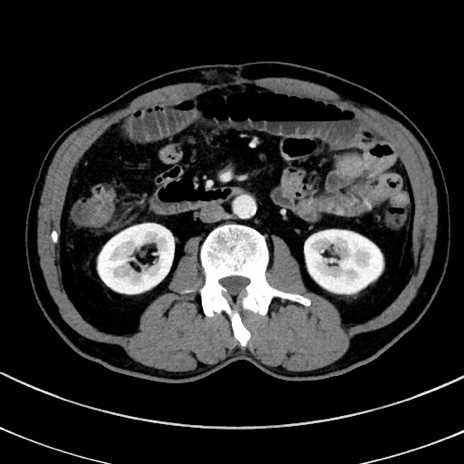

症例8(横断像)

【症例】 60歳代男性

【主訴】 黒色吐物

【現病歴】 4日前から嘔気自覚、2日前の朝食後にも嘔気あり、自分で手で嘔吐反射起こし嘔吐したところ血が混ざっていたため受診。

【既往歴】 5年前汎発性腹膜炎を伴う急性虫垂炎で手術、高血圧、前立腺肥大症、高脂血症

【身体所見】 腹部正中に手術癩痕あり 腹部平坦・軟圧痛なし膨満感あり

【データ】WBC 8400、CRP 4.54